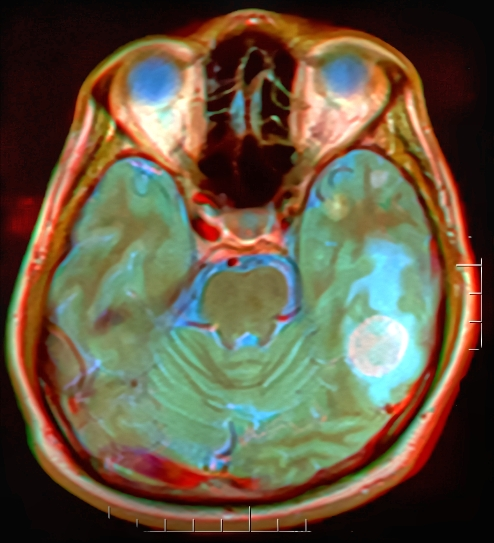

Brain Tumor

Brain Metastases

MRI brain tumor.